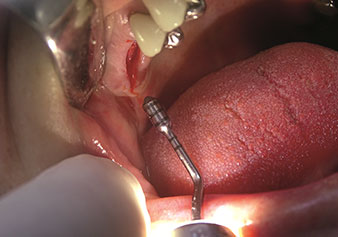

Un’applicazione che viene spesso sottovalutata è l’estrazione atraumatica di radici di denti o frammenti di radici nell’ambito della gestione alveolare. I periotomi sottili, che sono attualmente disponibili in due versioni (EX1 ed EX2 di W&H), possono essere, inoltre, utilizzati per rimuovere con facilità denti che hanno precedentemente subito uno specifico trattamento endodontico o con radici anchilosate. Ne consegue l’estrazione di alveoli in cui i tessuti duro e molle sono entrambi completamente intatti in quanto è generalmente possibile evitare la riflessione.

Ciò pone le basi ottimali per un trattamento con impianto immediato o successivo (Figure 1 e 2 inserite grazie alla gentile concessione del Dott. Torsten Conrad, Bingen a. Rhein).

Foto: © Dott. Torsten Conrad (Bingen a. Rhein)